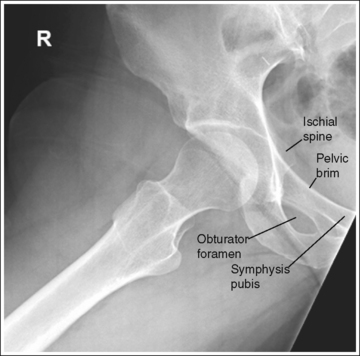

The pelvis demonstrates an AP projection. The ischial spine is aligned with the pelvic brim, the sacrum and coccyx are aligned with the symphysis pubis, and the obturator foramen is open.

• Detecting pelvis rotation. Rotation on an AP hip projection is initially detected by evaluating the relationship of the ischial spine and the pelvic brim, the alignment of the sacrum and coccyx with the symphysis pubis, and the degree of obturator foramen demonstration. If the patient was rotated toward the affected hip, the ischial spine is demonstrated without pelvic brim superimposition, the sacrum and coccyx are not aligned with the symphysis pubis but are rotated away from the affected hip, and the obturator foramen is narrowed (see Image 1). If the patient has been rotated away from the affected hip, the ischial spine is not aligned with the pelvic brim but is demonstrated closer to the acetabulum, the sacrum and coccyx are not aligned with the symphysis pubis, but are rotated toward the affected hip, and the obturator foramen is widened (see Image 2).

The ischial spine is not aligned with the pelvic brim but is demonstrated closer to the acetabulum, the sacrum and coccyx are not aligned with the symphysis pubis but are rotated toward the affected hip, and the obturator foramen is clearly demonstrated. The patient was rotated away from the affected hip (left posterior oblique [LPO] position).

Rotate the patient toward the affected hip until the ASISs are positioned at equal distances from the imaging table.